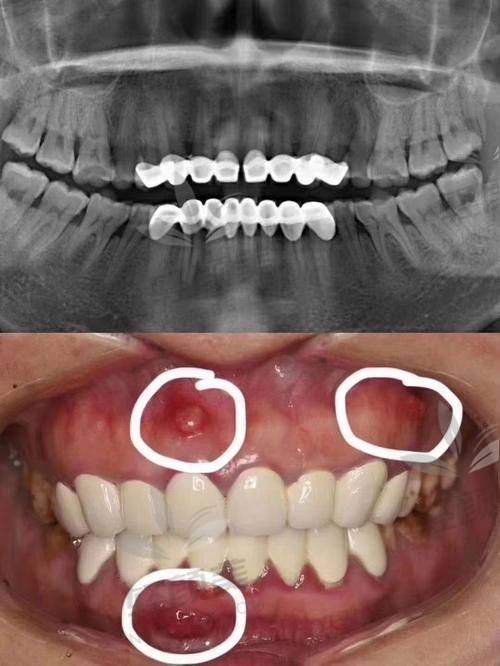

? 诊前方案明确:别听忽悠“补牙变根管→强制烤瓷”,一定要看片+确认破坏程度。

? 资质正规:认准有《医疗机构执业许可证》的正规口腔医院或门诊部,别拿牙当小白鼠。

? 医生经验:别让实习牙医打开你嘴巴30分钟,要问清楚是否有超5年以上修复经验。